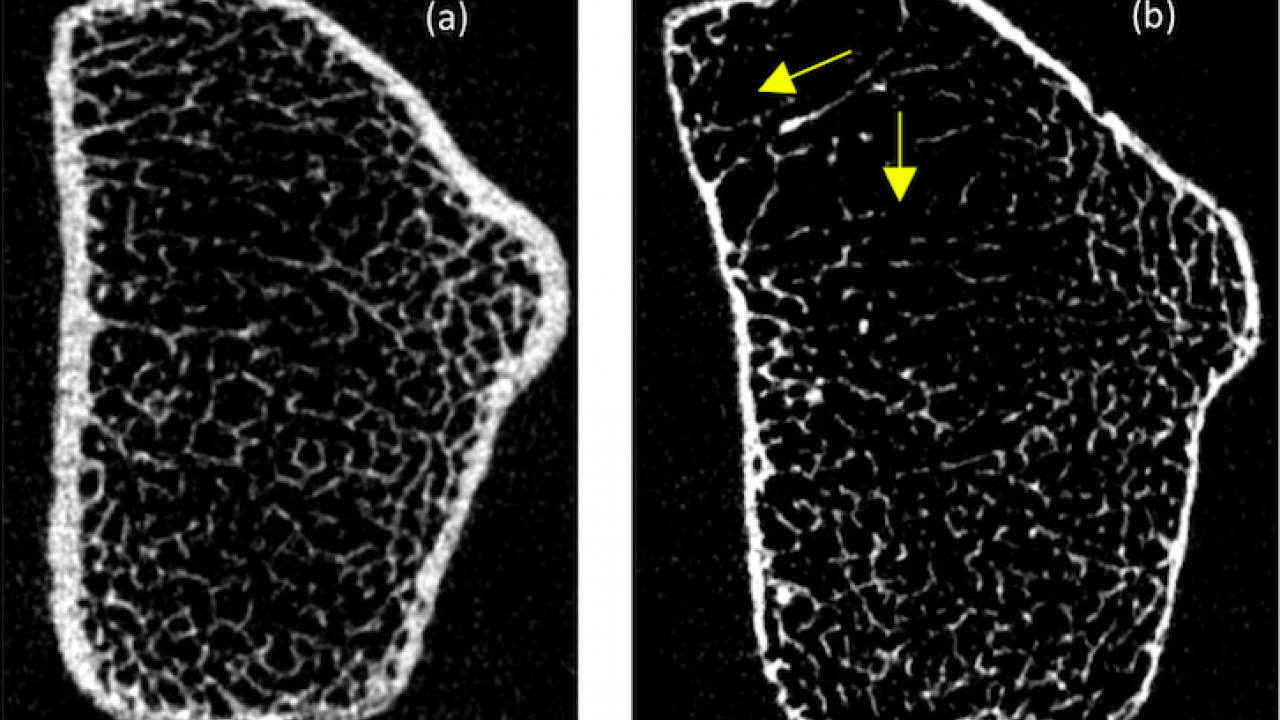

Osteoporosis In Pregnancy Semantic Scholar